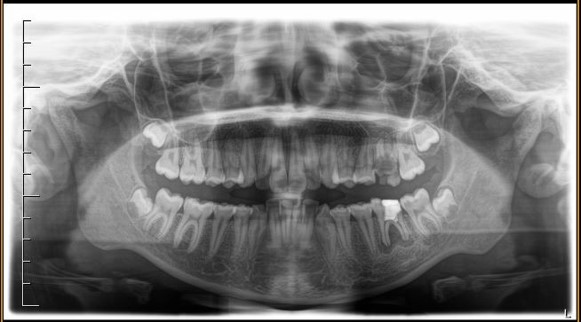

Ortopanoramica pre-trattamento della paziente. I due primi molari sinistri appaiono irrimediabilmente compromessi da carie destruenti

Fig. 1 Ortopanoramica pre-trattamento della paziente. I due primi molari sinistri appaiono irrimediabilmente compromessi da carie destruenti